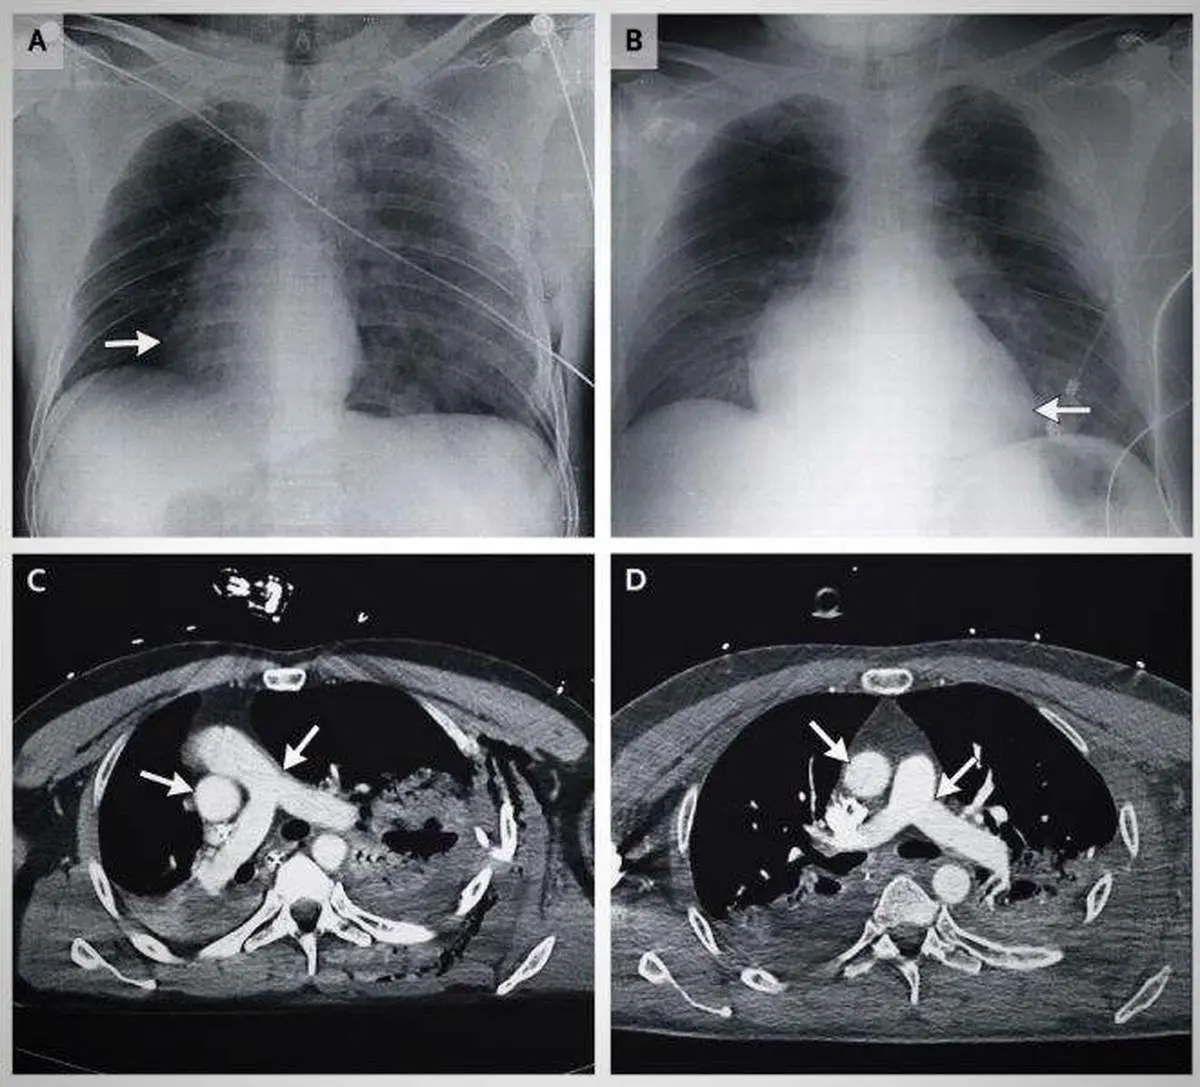

به گزارش منیبان؛ در ماه می سال 2014، یک اتفاق جالب در تاریخ پزشکی به ثبت رسید. قلب یک مرد بعد از تصادف با موتورسیکلت 90 درجه داخل قفسه سینه اش چرخیده بود و به سمت راست رفته بود. این گزارش در ژورنال پزشکی بریتانیا به ثبت رسانده شد.

سی تی اسکن ها نشان داد که قلب 90 درجه به سمت راست قفسه سینه رفته است. این مرد 48 ساله که داستان عجیبش را در این بخش می خوانید بر اثر تصادفی در کشور ایتالیا ضربه شدیدی خورده بود که سریع او را به بیمارستان رساندند. زمانی که پزشکان شروع به درمان کردند، متوجه شدند که اتفاق جدیدی در قفسه سینه او رخ داده است.

زمانی که خواستند ضربان قلب او را اندازه بگیرند، متوجه شدند قلبش در قسمت راست بدن است و در سمت چپ، هیچ اثری از قلب وجود ندارد. سپس او را برای آزمایش اشعه ایکس و سی تی اسکن آماده کردند. سی تی اسکن هم دقیقا همین موضوع را نشان داد. این گزارش در مجله پزشکی به ثبت رسانده شد.

زمانی که اسکن کل بدن انجام شد، متوجه شدند که رگ های بزرگ و اصلی سرخرگ و آئورت، هر دو همراه با قلب به سمت راست رفته اند. این فرد مشکل ریه پیدا کرده بود و چندین شکستگی در دنده هم برایش اتفاق افتاد و به دلیل تصادف، طحال او هم آسیب دیده بود اما با وجود چنین آسیب دیدگی های شدیدی، باز هم زنده مانده بود، هوشیار بود و متوجه اتفاقات اطرافش بود.

پزشکان بعد از آزمایشات متعدد متوجه شدند که این اتفاق در حین تصادف رخ نداده است، بلکه چند دقیقه بعد از تصادف قلب این مرد چرخش داشته است. به این صورت که هوا از سمت ریه آسیب دیده به فضای قفسه سینه وارد شده بود و همین هوای بسیار زیاد، قلب را به سمت راست هل داده بود. سپس پزشکان هوای اضافی را از قفسه سینه مرد بیرون کشیدند.

جالب است بدانید که بعد از 24 ساعت، قلب این مرد به سر جای اصلی خودش برگشت. آزمایشات نشان داد که قلب این مرد کاملا سالم است و فقط تعداد کمی از رگ های خونی او به دلیل فشار خون حاصل از چرخش، دچار مشکل شده بودند.